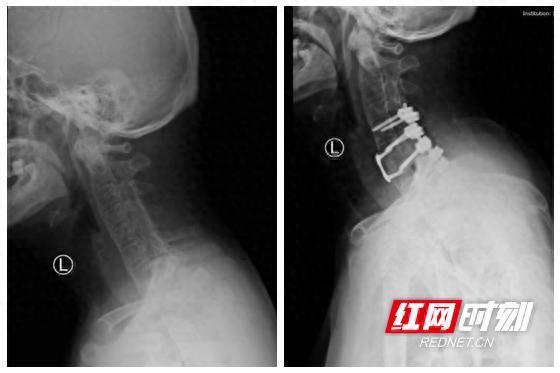

手术前后对比图

患者入院后,骨科常德病区迅速将影像资料上传至中南大学湘雅医院骨科,脊柱外科专家吴天定副教授第一时间评估患者得出结论:考虑该患者颈椎骨折脱位不稳定,合并有强直性脊柱炎、骨质量差、融合率低的特点,常规的单纯前路或者后路固定融合无法保证颈椎的融合和稳定性,需通过前后路手颈椎术给予坚强的内固定,重建颈椎稳定性,保证颈椎复位稳定质量,提高颈椎融合率,从而为保障神经功能正常创造条件。其次,颈胸交界区术中透视困难,术中极易损伤椎动脉导致大出血,再加上脊柱小关节的融合(竹节样)改变,失去了术中可参考的解剖标志,所以该手术难度高、风险大。

吴天定副教授根据患者资料制定了详细手术方案。骨科常德病区在完善相关术前准备后,1月21日,吴天定副教授到达常德,为患者实施“颈椎前后路联合复位内固定融合术”。该手术一次性完成颈椎复位、神经减压及稳定性重建,未出现任何并发症,术后3天患者即可佩戴支具下床活动,恢复效果显著。